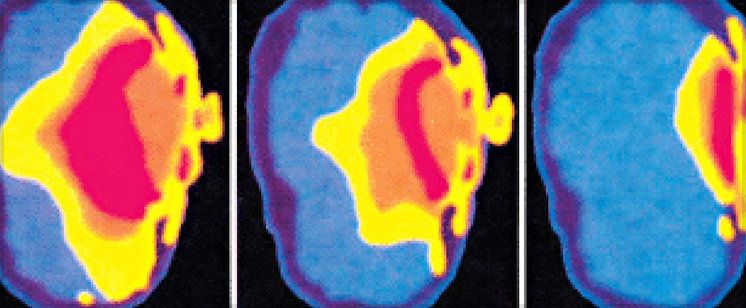

New analysis in American Journal of Epidemiology finds doubling of brain cancer in persons using cell phones over 558 hours